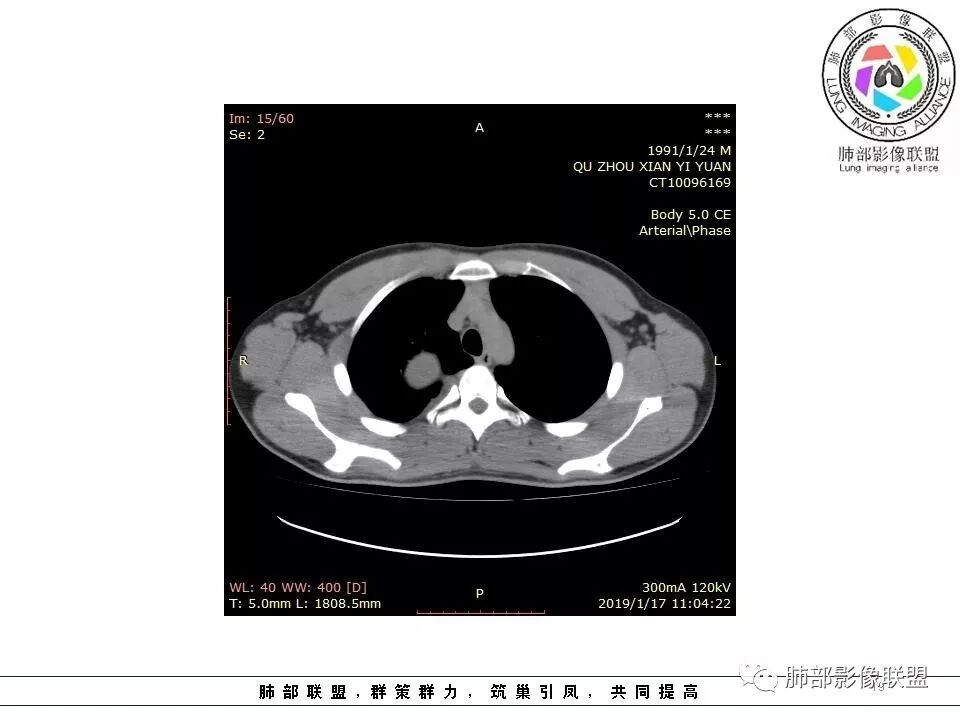

【每日晨读】脊柱旁肿瘤之争:您能一锤定音吗?

7.17晨读病例

1.右上胸内脊柱旁类圆形肿块,质地似乎比较坚实,密度稍显不均,但未显示明确的坏死。

如此密度形态的病灶位于肺边缘首先应当想到孤立性纤维瘤,可相邻胸膜未见明显的异常强化和胸膜方向延伸。

注意所谓“胸膜尾征”的概念及形成机制与“脑膜尾征”是大不相同的。

2.肋间动脉病供血也提示肿块来自后纵隔?